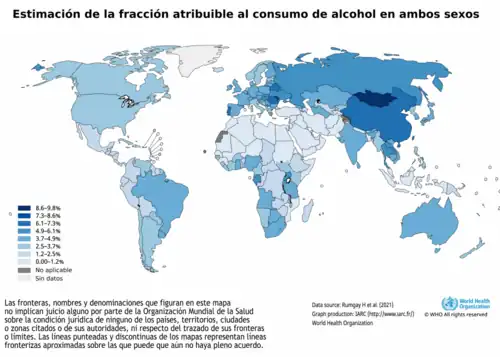

El 3,6% de todos los casos de cáncer y el 3,5% de las muertes por cáncer en el mundo se atribuyen al consumo de alcohol (más concretamente, al acetaldehído, un derivado metabólico del etanol).[6] 740.000 casos de cáncer en 2020 o el 4,1% de los nuevos casos de cáncer se atribuyen al alcohol[3][2]

El consumo excesivo de alcohol, consistente en 15 o más bebidas a la semana en el caso de los hombres u 8 o más bebidas a la semana en el caso de las mujeres, fue el que más contribuyó a la incidencia del cáncer en comparación con el consumo moderado. La tasa de casos relacionados con el alcohol es de 3:1 entre hombres y mujeres, especialmente en los cánceres de esófago e hígado.[3]

Prevalencia mundial de diagnósticos de cáncer atribuidos al consumo de alcohol

En 2020, se identificaron aproximadamente 740 000 casos de cánceres relacionados con el alcohol en todo el mundo[8][9] con

- 58% de los casos (430.000) residiendo en Asia

- 25% de los casos (180.000) residen en Europa

- 8% de los casos (60,000) que residen en América del Norte

- 5% de los casos (39.000) residen en América Latina y el Caribe

- 3% de los casos (23.000) que residen en África

- 1% de los casos (7.000) residentes en regiones denominadas "otras".

Más de las tres cuartas partes de los 740.000 casos fueron en hombres.[10]